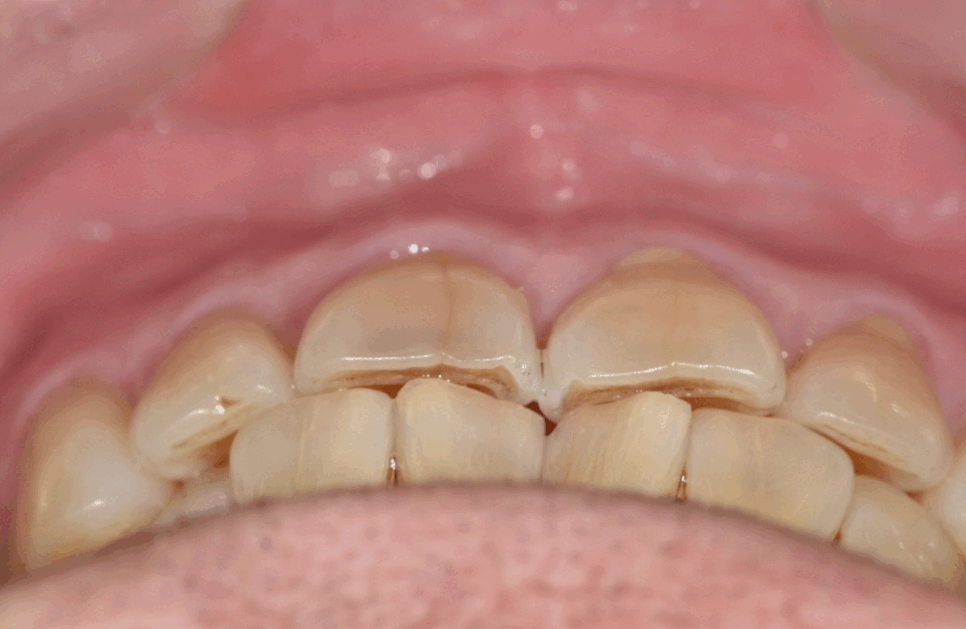

식사할 때마다 마치 못 위에 망치를

계속 내리치듯, 앞니 끝끼리 정면으로 부딪히고 있었던 겁니다.

이런 충격이 오랜 시간 계속되면 어떻게 될까요?

유리도 계속 두드리면 금이 가듯이,

치아도 조금씩 금이 가기 시작합니다.

240605

처음엔 눈에 안 보일 정도로 미세하지만,

충격이 계속 쌓이다 보면 어느 날 갑자기 '뚝' 하고 깨질 수 있습니다.